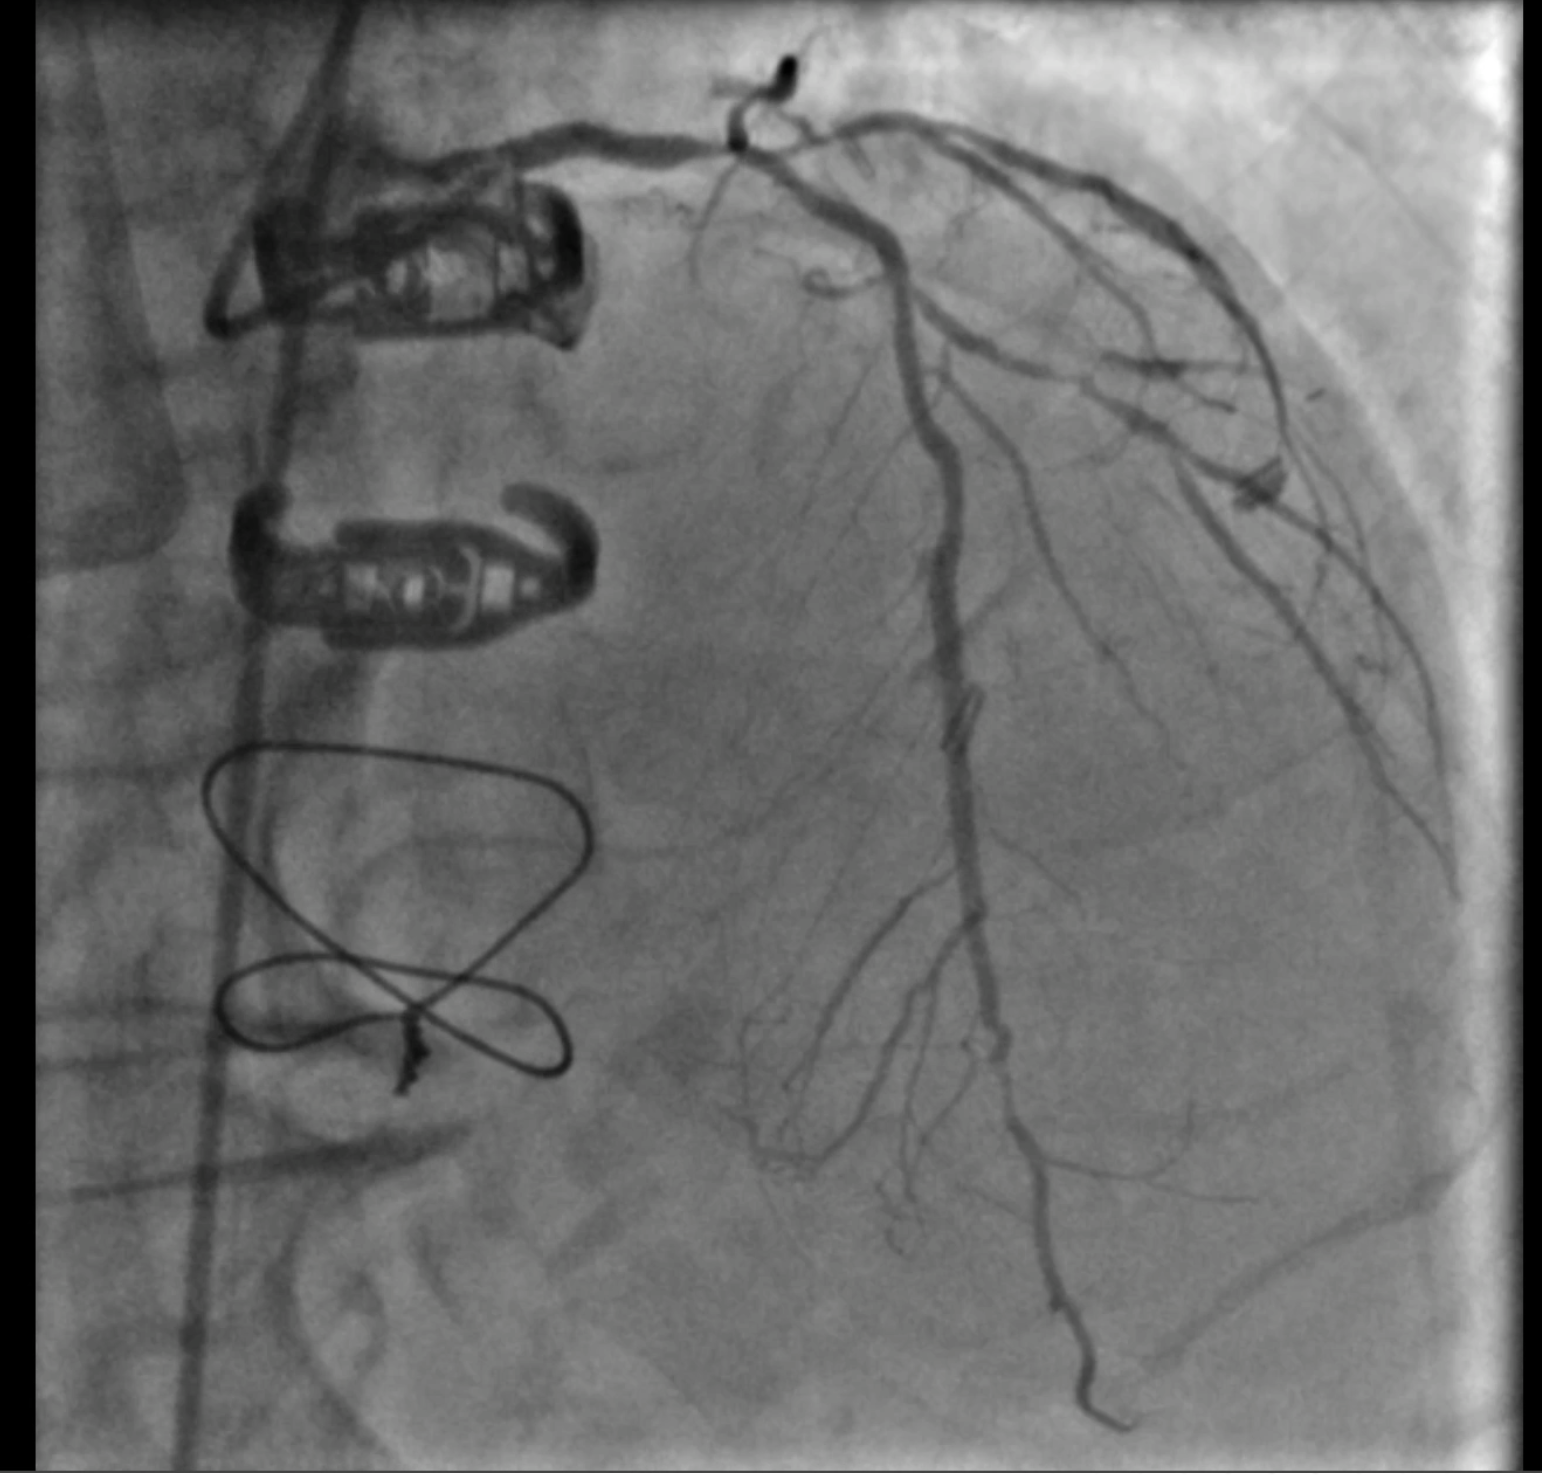

At the first encounter, coronary angiography revealed a left main bifurcation lesion (Medina 1-1-1) with 99% ostial stenosis of the LCX and severe stenosis in the proximal LAD and the 2nd diagonal branch. Collateral circulation was observed from the LAD and LCX to the distal RCA. Right coronary angiography showed a proximal CTO with a J-CTO score of 3 due to calcification, bending, and lesion length. The LIMA was not grafted to the LAD.

At the 1st encounter, RCA CTO PCI was performed with a plan for staged PCI of the left system. Using a 7F AL 0.75 for strong support, an antegrade approach with a double-lumen microcatheter and parallel wire technique (Pilot 150) successfully crossed the lesion. Predilatation with a 1.5 ¡¿ 15 mm balloon was done. IVUS could not pass due to 360¡Æ calcification. Rotablation with a 1.25 mm burr was attempted but limited to mid-RCA. Two DES were implanted from mid to proximal RCA, followed by post-dilatation.At the 2nd encounter, RCA stents were patent. PCI was done on LM, LAD, and D2. D2 was treated with DCB. LAD predilatation followed by OCT showed severe 330¡Æ calcification (max thickness 1.04 mm, MLA 1.63 mm©÷). IVL with a 2.75 ¡¿ 12 mm balloon (30 pulses) achieved multiple calcium fractures. A 2.75 ¡¿ 33 mm DES was deployed with good OCT results.At the 3rd encounter, 6 months later, the patient presented with ADHF. Angiography revealed RCA ISR CTO at the mid-bending site. The lesion was crossed with a Pilot 200 wire; predilatation showed a dog-bone sign. We do balloon based strategy for plaque modification using cutting, scoring, and double-wire balloons. IVUS showed stent underexpansion with 270¡Æ calcification and distal RCA stenosis. IVL with 2.5 and 2.75 mm balloons optimized the lesion, followed by two DES from distal to mid RCA. Post-PCI IVUS confirmed good result.